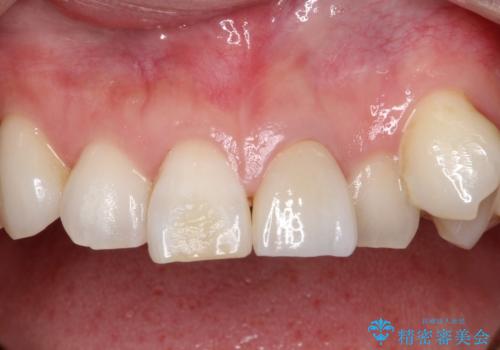

[前歯の変色] 前歯の見た目を改善したい

![[前歯の変色] 前歯の見た目を改善したいの症例 治療後](https://seimitsushinbi.jp/wp/wp-content/uploads/2021/05/1f01d9f0751d14a2f5d20ed7475c6e38-500x350.jpg?v=1622180216)